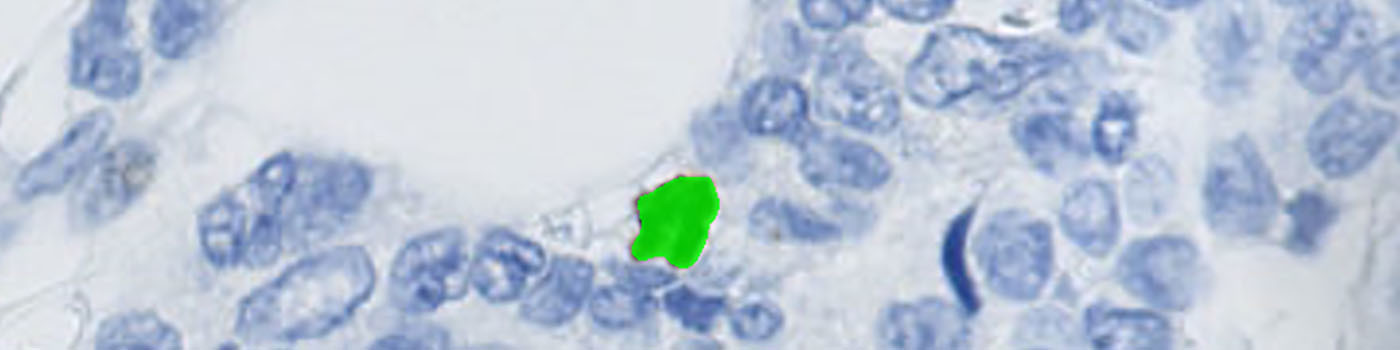

Tumor areas are manually outlined as regions of interest (ROIs) (see FIGURE 2). The ROIs are used for subsequent analysis limited to the inside of the tumor regions (see FIGURE 3).

Segmentation is performed of all nuclei (both PHH3 positive and negative). The method for nuclei separation which is based on shape, size and nuclei probability is used, employing a fully automated watershed-based nuclei segmentation technique. A post-processing step involving a morphological closing operation is applied to avoid counting nuclei in the late mitotic phase (anaphase and telophase) as two nuclei.

The number of positive PHH3 nuclei and the mitotic index is calculated.